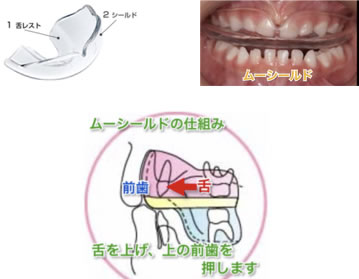

受け口の改善にはムーシールドがおすすめ!

当院では、ムーシールドを使用し、受け口の早期改善をすすめております。

4歳ぐらいから使用されると良いです。就寝時に使用します。大きい装置ですので、最初の1カ月は、朝までお口の中に入れておけない事があります。徐々に慣れてきます。小児期の受け口は、舌の位置が低く、下顎を前に押し出すように筋肉の圧力が働きます。ムーシールドの装着で舌の位置を上げ、口の周りの筋肉を正常化することで、上顎の成長を促し、下顎の成長を抑える効果があります。

これらの機能により、「歯並びを整える」というのではなく、「子供の顎の成長を利用して、上下の歯の咬み合わせの関係を正常なものにしようとさせる」という目的で使用するものです。

しかしこの装置で将来にわたって100%咬み合わせ異常が改善されるわけではありません。小学校に入学されたあたりから、再び装置を使った矯正に移行することも多いです。そのような場合でも早くから矯正を始めておくと、無理なく矯正治療が進みますので、3歳頃から矯正治療をご相談されることをお勧めします。